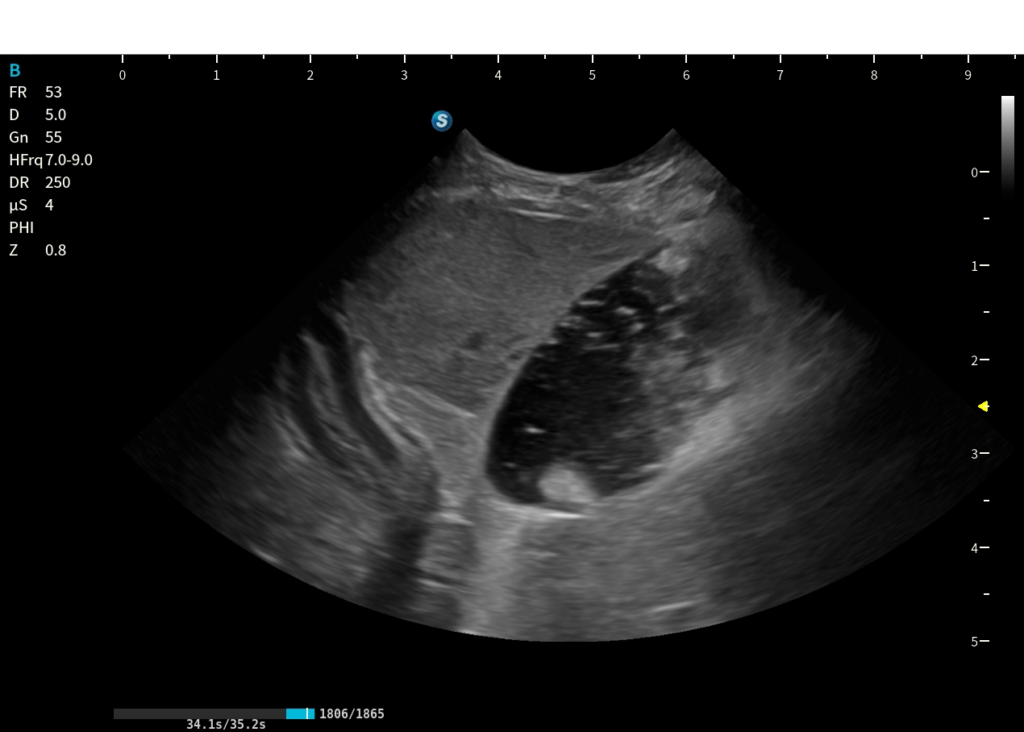

Routine e funzioni avanzate

20260227 095005 ABD 12